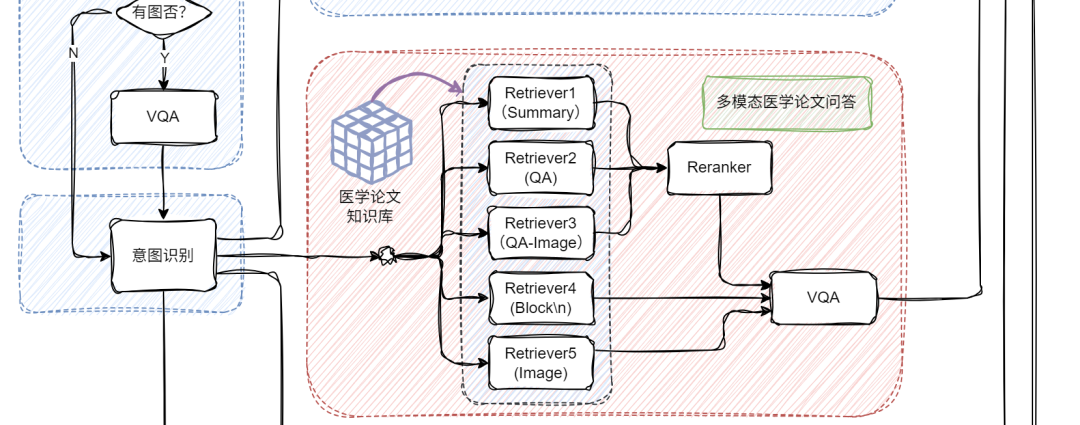

当用户提问中包含图片时,系统会自动触发 VQA,对图像进行结构化信息提取,挖掘上下文关键内容;若没有图像,就跳过这步,直接进入文本处理环节,效率UPUP!

接下来,系统通过意图识别模块,将不同类型的问题智能分流:

📌论文问答? 走传统 RAG 路线!向量检索+大模型生成,精准提取相关文献内容。

📌统计问答? 开启 SQL 模式!从提问中抽取结构化信息(如指标、维度、过滤条件),自动生成 SQL 查询,查询结果再由大模型“翻译”成自然语言,一目了然!

这部分我们聚焦在医学论文问答场景,结合文本+图像的多模态输入,构建一个更智能的 RAG 系统,并支持返回可视化图表。整体框架的细节如下:

首先,我们将PDF解析成文本和图像;文本部分我们可以通过\n切分、LLM(总结)和 LLM(QA)等方式构造不同的block文本节点;图像部分我们通过多模态大模型构建相应的QA文本节点qapair_img和图像根节点;接下来,我们将所有节点统一编码入库,并通过多路召回机制进行语义匹配与内容检索;在召回阶段之后,引入重排序机制,进一步优化检索结果的相关性与准确性;最后,系统会将用户的查询(query)与召回得到的上下文(context)内容一并输入至多模态大模型,由其生成最终答案。整体代码实现如下:

多模态 + 统计分析:双剑合璧,能力翻倍!

在已有的多模态论文问答系统基础上,我们进一步集成了统计分析机制,让系统不仅能“看图识意”,还能“分析数据、输出结论”。这样一来,系统就不仅仅是一个问答助手,更像是一个拥有知识库+分析大脑+视觉理解力的超级 AI 学者 。主要实现代码如下:

def build_paper_assistant():llm = OnlineChatModule(source='qwen', stream=False)vqa = lazyllm.OnlineChatModule(source="sensenova",\model="SenseNova-V6-Turbo").prompt(lazyllm.ChatPrompter(gen_prompt))with pipeline() as ppl:ppl.ifvqa = lazyllm.ifs(lambda x: x.startswith('<lazyllm-query>'),vqa, lambda x:x)with IntentClassifier(llm) as ppl.ic:ppl.ic.case["论文问答", paper_ppl]ppl.ic.case["统计问答", sql_ppl]return ppl